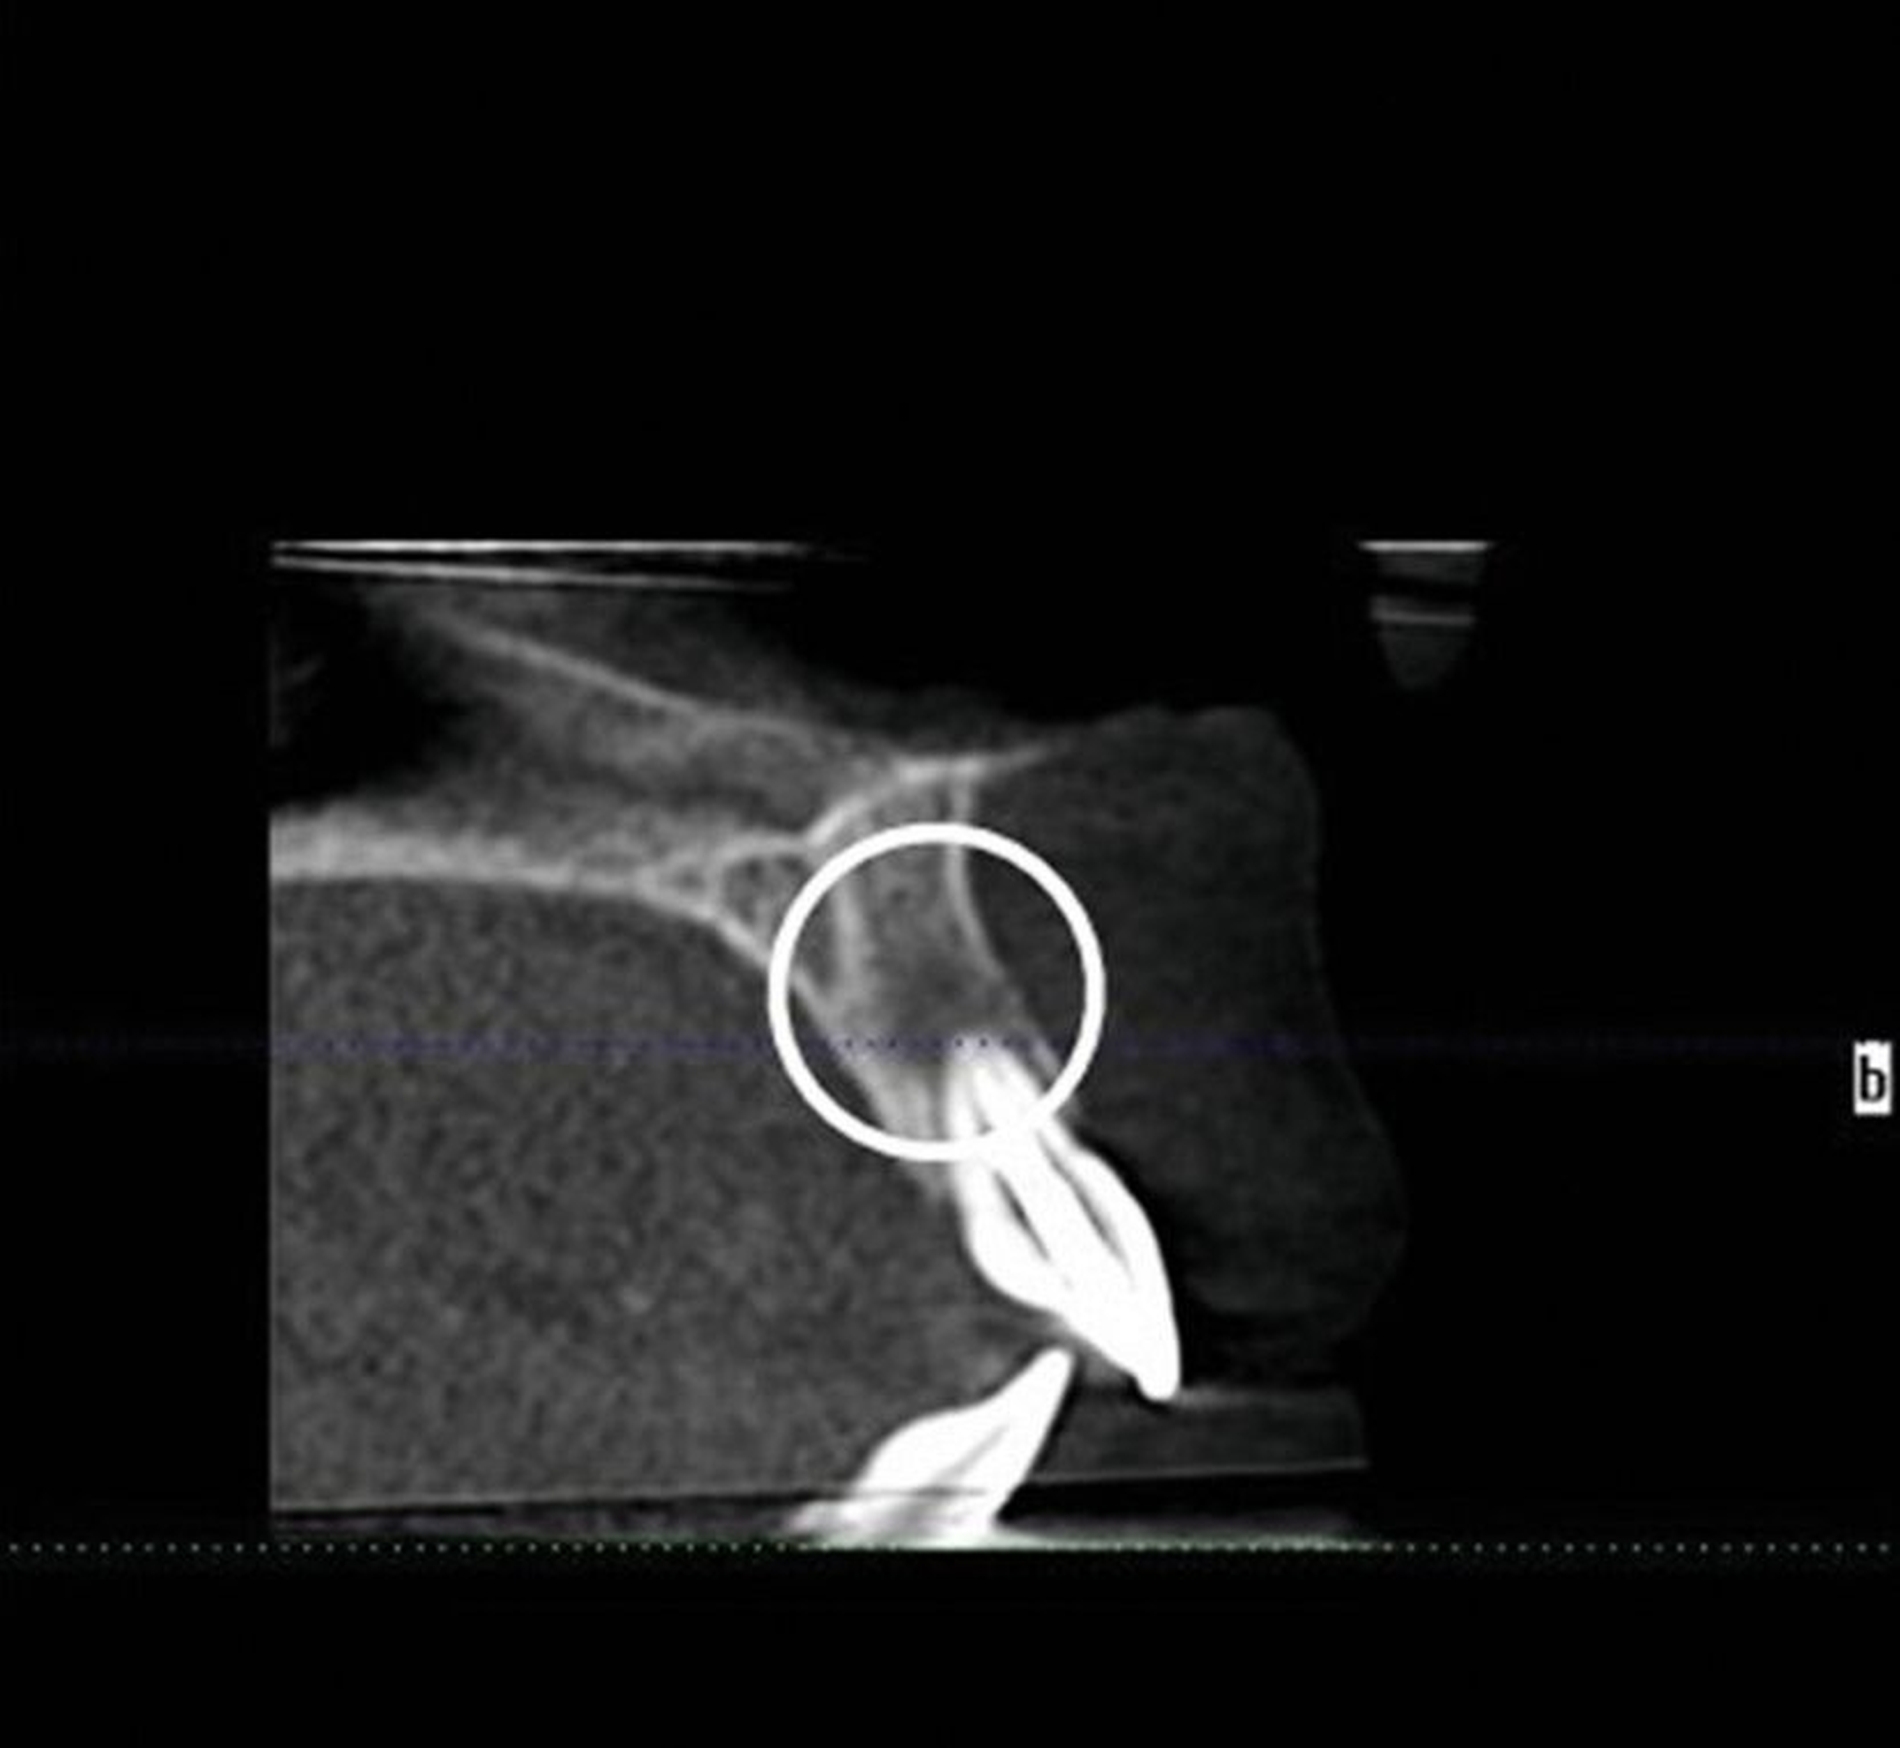

Zur weiteren Abklärung wurde eine dreidimensionale Aufnahme durchgeführt (DVT). Dabei bestätigte sich die erhebliche Osteolysezone im apikalen Bereich des vormals traumatisierten Zahnes 21. Der Zahn 13 stellt sich hoch verlagert am Nasenboden dar, während es bei dem persistierenden Milchzahn 53 zu einem natürlichen Lückenschluss in regio 13 gekommen ist (Abbildung 2).

Wir entschieden uns für ein zweizeitiges Vorgehen mit Entfernung des Zahnes 21 und Ausräumung der ausgedehnten entzündlichen Läsion im apikalen Bereich mit Anfrischung des Knochens, um so eine entzündungsfreie Situation vor Transplantation zu erreichen. Der Zahn 21 wurde provisorisch als Pontic wieder eingesetzt, um eine weitere Retraktion des Weichgewebes in regio 21 zu vermeiden (Abbildung 3B).